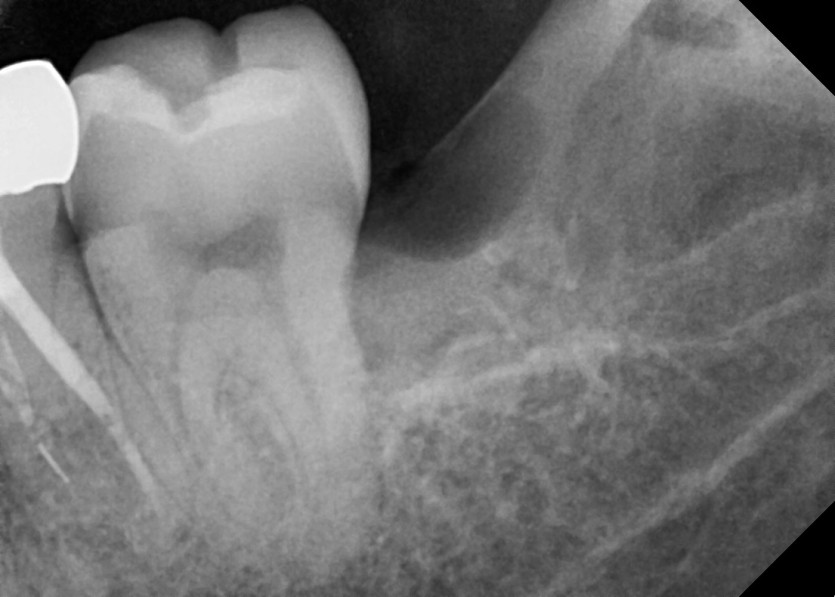

#38, 48 사랑니 발치

구강 외과 전문의가 당일 발치했습니다.